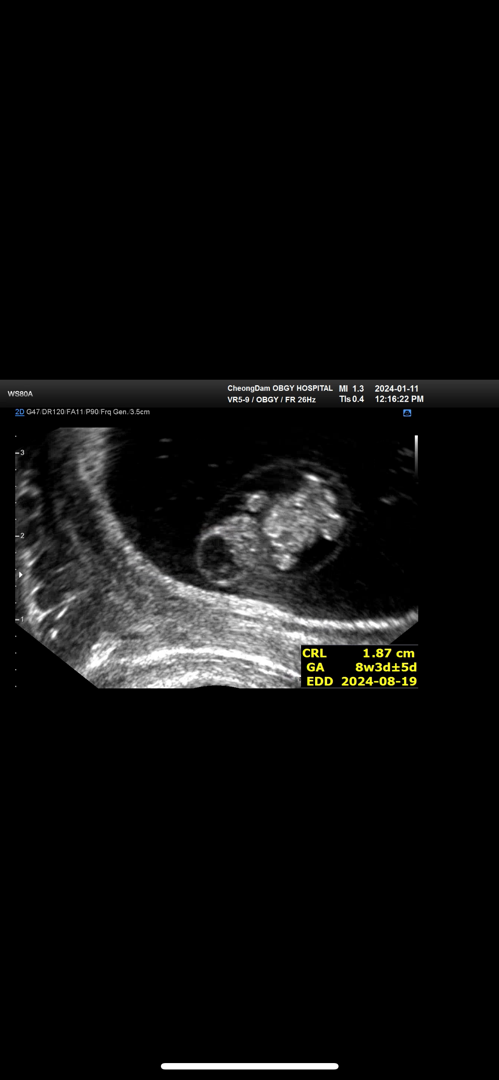

8주차 젤리곰 너무 기여워요

팔다리가 생기기 시작하니까 뭔가 진짜 이제 사람인 것 같고 귀엽다는 생각도 들구 그러네요! 전까지는 그냥 뭔가 신기하다? 정도에 저 작은 세포같은게 날 이렇게 힘들게하나 (입덧) 싶기만 하고 별 감흥이 없었는데.. 이번에 갔을 때 혼자 꼬물꼬물 거리는것도 보구 팔다리 생겨난것도 보니까 뭔가 뭉클해요 아가야 건강히 자라렴

질초음파로 봤어용~~